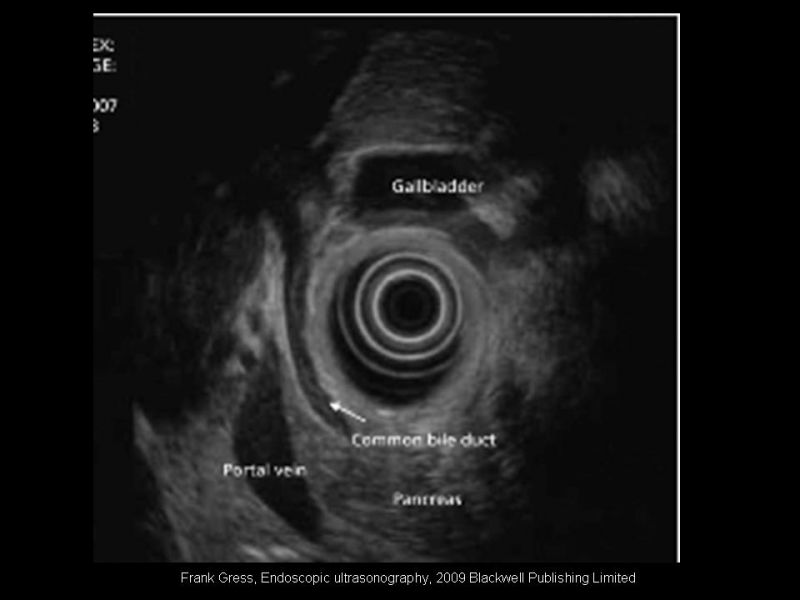

Rol actual de la endosonografía en patología biliopancreática

Especialidad: Hepatobiliopancreático | Autor: Dr. Rodrigo Subiabre Ferrer